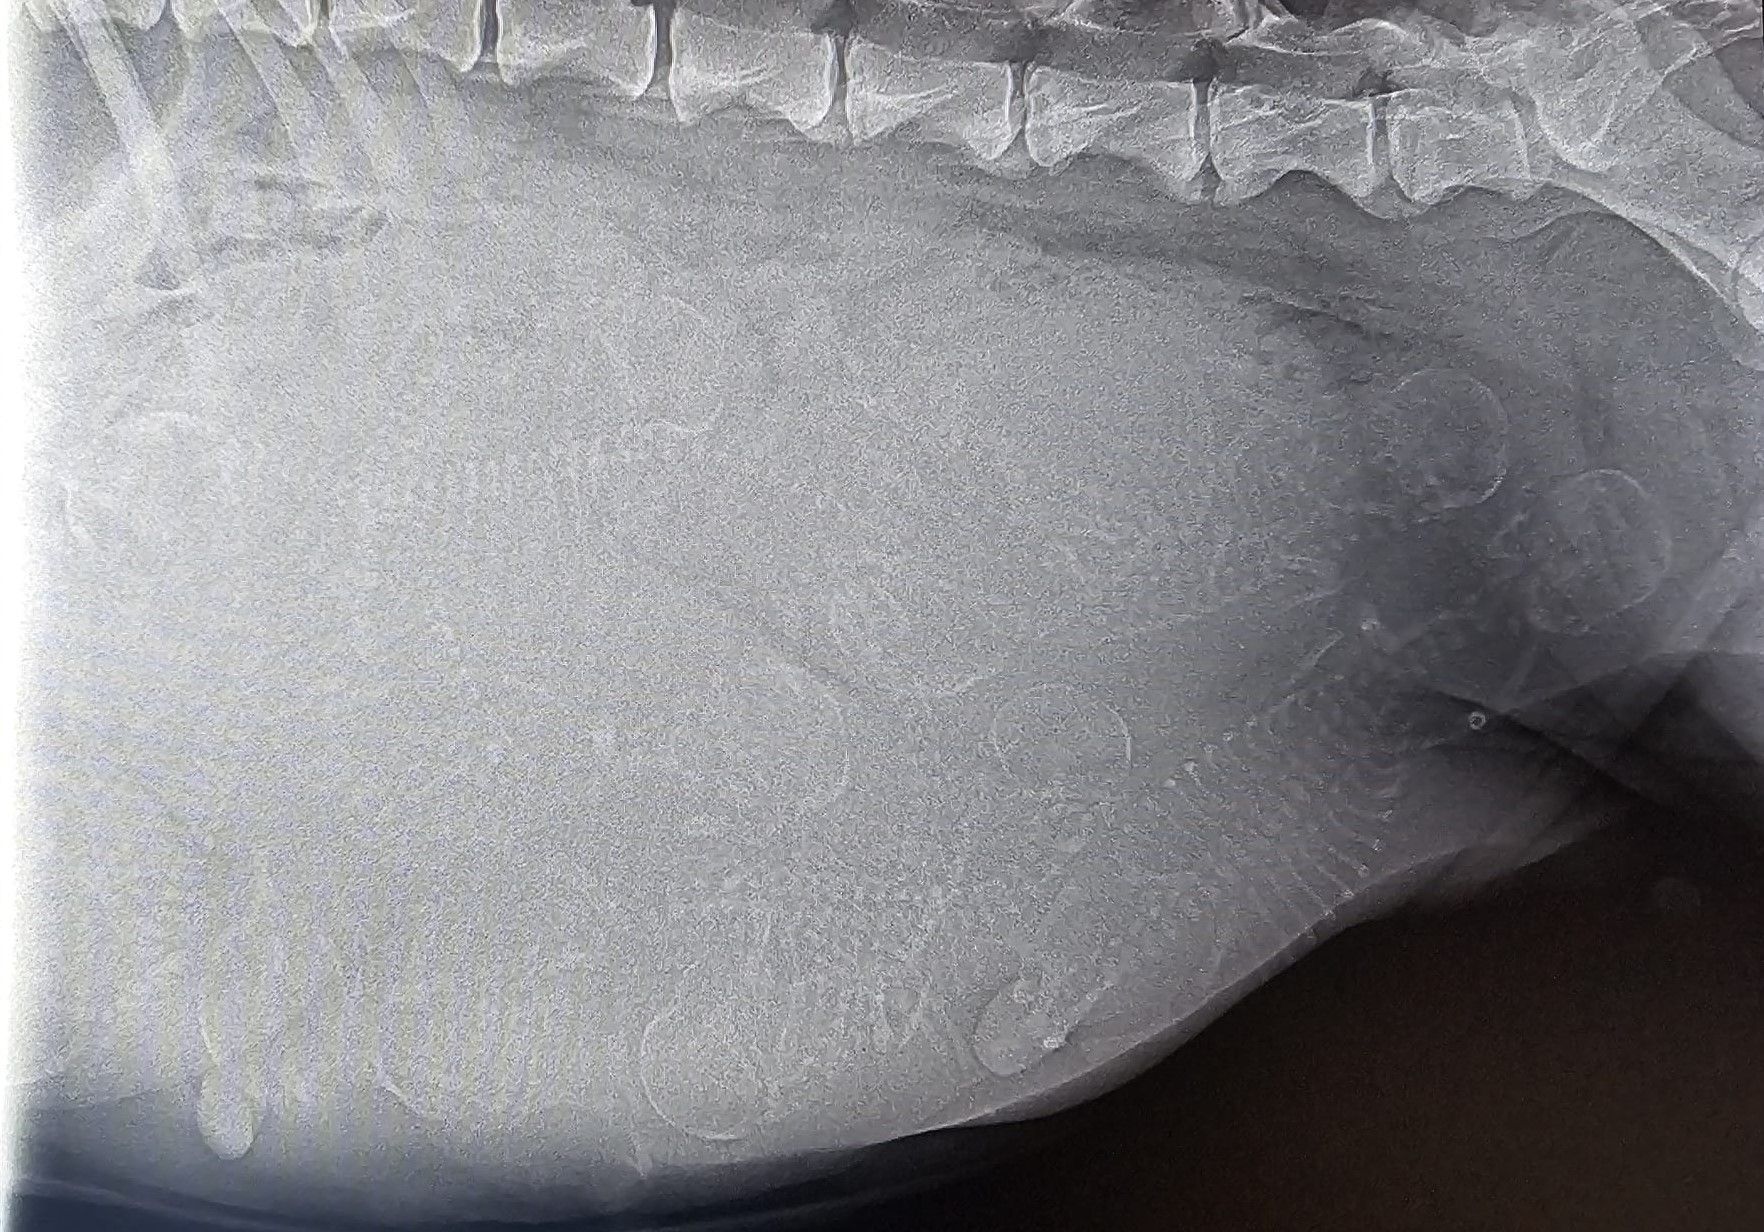

Heute am Tag 51 der Trächtigkeit waren wir mit Bones beim Tierarzt um die obligatorische Röntgenuntersuchung durchführen zu lassen.

Alles ist bestens verlaufen, es werden wohl um die 10 Welpen werden...

Am 22.04.2024 erfolgt der letzte Gesundheitscheck für Bones beim Tierarzt. Bei dieser Gelegenheit wird auch gleich eine Röntgenaufnahme gemacht um die Anzahl der Welpen abzuschätzen.